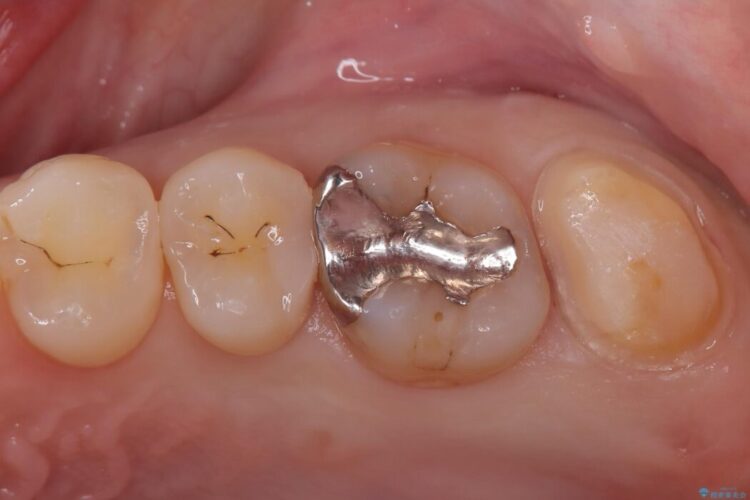

部分的断髄法(MTAの使用): ラバーダム防湿を行い、無菌的な環境下で虫歯を慎重に除去。神経の露出を確認した後、炎症を起こしている一部の神経のみを除去し、残りの健全な神経を保護するためにMTAセメントを充填しました。これにより、神経の機能を維持し、歯を内部から守ることが可能となりました。

経過観察と土台作り: 一定期間の経過を観察し、痛みや炎症がないことを確認。神経の生存を確認した上で、セラミックを支えるための土台を精密に構築しました。